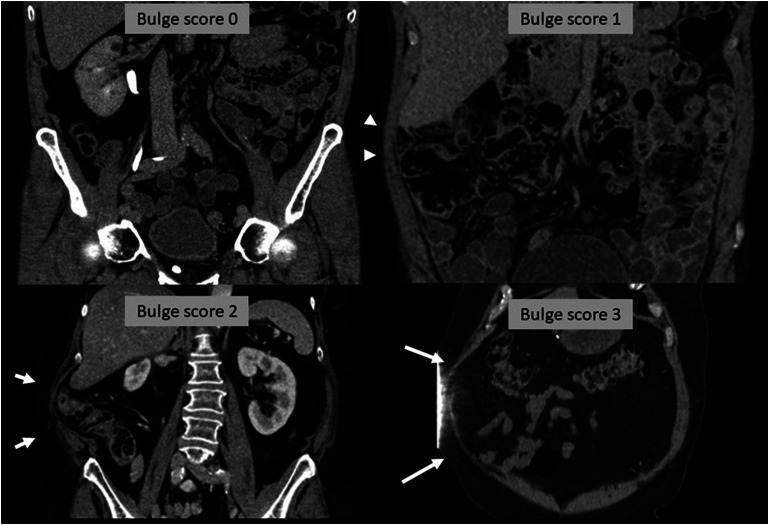

Purpose: To characterise muscular changes related to postoperative abdominal bulging and design a visual scoring system to grade bulge on postoperative CT scans.

Results: Common features of abdominal bulging were extracted and a four-tier visual score ranging from normal abdominal wall to severe bulge was developed. Among the patients, ∼70% had a normal abdominal wall, ∼25% had bulge score 1, ∼7% score 2, and ∼1% score 3. Inter-rater agreement was 73.5%, with Fleiss' Kappa 0.44.

Conclusion: Features of bulge were reduced muscle thickness and ipsilateral gravitational slump affecting part or all of the lateral abdominal wall. The proposed scoring system demonstrated only moderate inter-rater reliability in this pilot setting. Further research on postoperative abdominal wall changes is needed before implementing imaging-based assessments in clinical care.